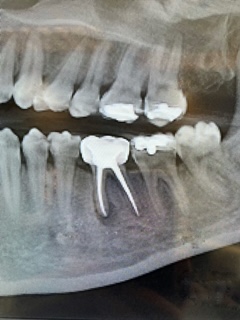

When radiographic imaging reveals decay extending into the second layer of the tooth (dentin) while the nerve remains healthy, Dr. Toler recommends removing the decay, sterilizing the area with ozone, and restoring the tooth using a biocompatible, metal-free, and fluoride-free material.